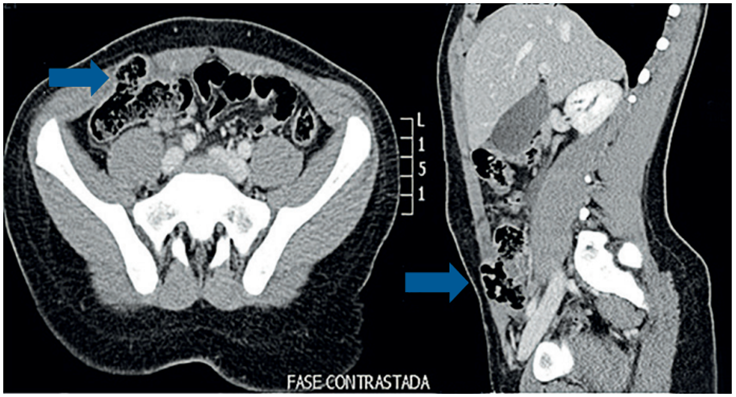

Realizan tomografía computarizada (TC) de abdomen que muestra escaso líquido libre en el fondo de saco derecho y lo que consideraron una “hernia de Spiegel” (Figura 2).

Por la relación con el trauma y la ausencia de hernia previa, se hizo diagnóstico de hernia traumática y se llevó a cirugía donde se encontró un gran defecto de la pared abdominal, desde el flanco derecho hasta el hipogastrio, con avulsión y desgarro del recto anterior derecho, hematoma de los tejidos blandos adyacentes, del ciego, del mesocolon y del apéndice cecal, los cuales estaban involucrados en el defecto. Se corrigió el defecto con cierre primario sin material protésico, con buena evolución posquirúrgica. Fue dado de alta al día siguiente de la intervención y en el seguimiento a los 40 meses, continua sin síntomas ni signos de recidiva.